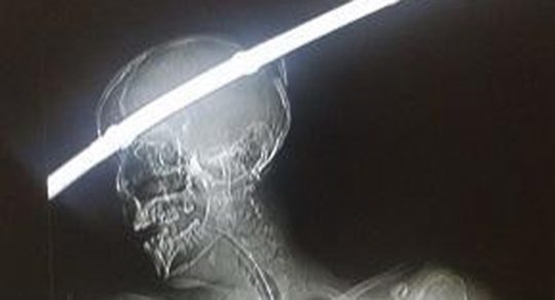

لحسن الحظ، تمكن الأطباء من استخراج القضيب الحديدي، الذي أظهرته الأشعة السينية وهو يخترق جمجمة ودماغ محمد من ناحية إلى أخرى، باستخدام المنظار وجراحة استمرت ساعتين ونصف.